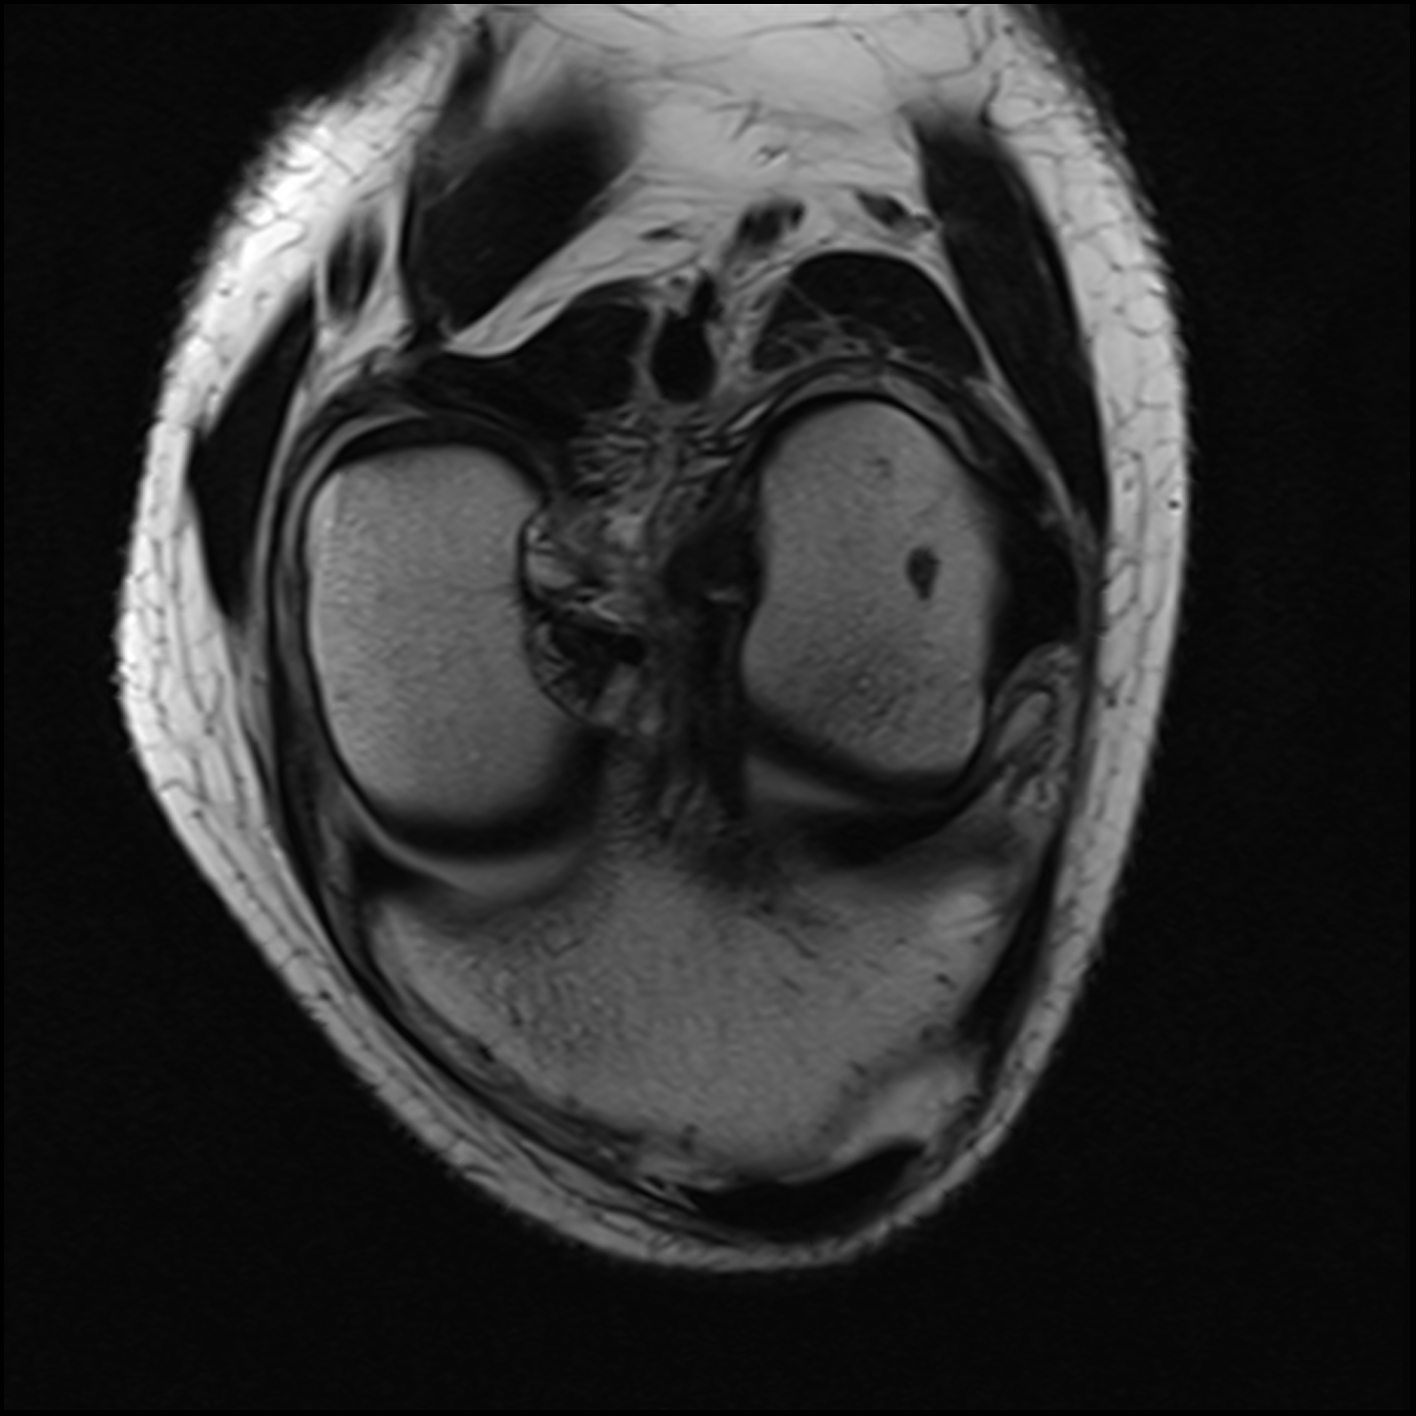

December 2019 MRI

IMPRESSION

- Medial: Nondisplaced horizontal longitudinal tear extending obliquely to the

undersurface of the meniscal body and posterior horn segments. No chondral erosion or thinning. Intact root ligaments. - Intact anterior cruciate ligament. Normal posterior cruciate ligament. Intact medial

lateral supporting structures. - No joint effusion or synovitis. No periarticular muscle injury. No osseous contusion

or stress injury. Minimal fluid in the semimembranosus-medial gastrocnemius bursa. No

frank Baker's cyst.